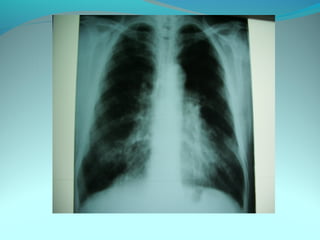

Image radiologique bilatirale a type d’opacité nodulaire occupant les

2/3 sup du poumon droit et la ½ sup du P G confluante par pour

former de grosses opacités

DIAGNOSTIC:

Tuberculose pulmonaire bilateral

Pneumonie bilaterale